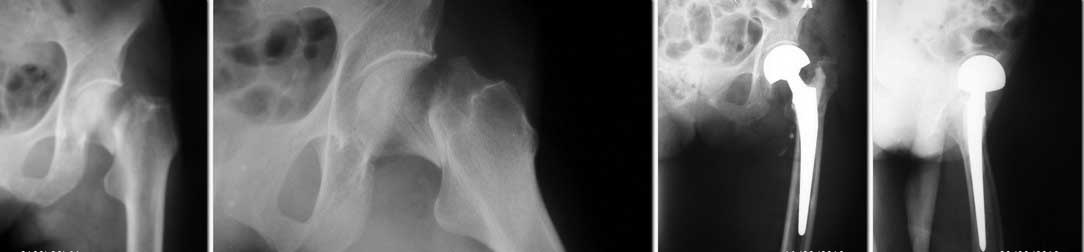

Уважаемые коллеги. Поделитесь опытом... Имеем в отделении вот такой результат

эндопротезирования. Какие рекомендации для больной в дальнейшем и чего следует ожидать при

такой рентгенологической картине? Пациентке 76 лет, вес около 50 кг, операция через 5 недель

после травмы.